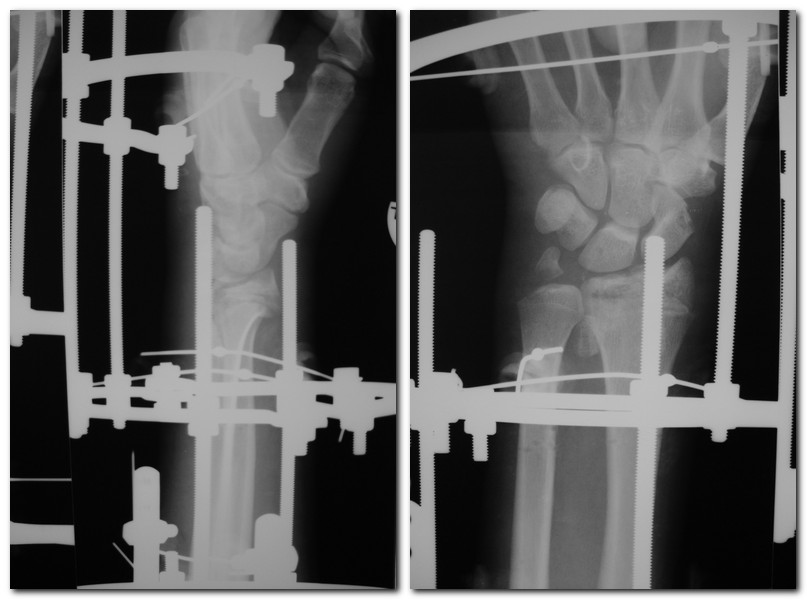

[Ortho] Закрытый оскольчатый перелом дистального метэпифиза лучевой кости

снимки в аппарате